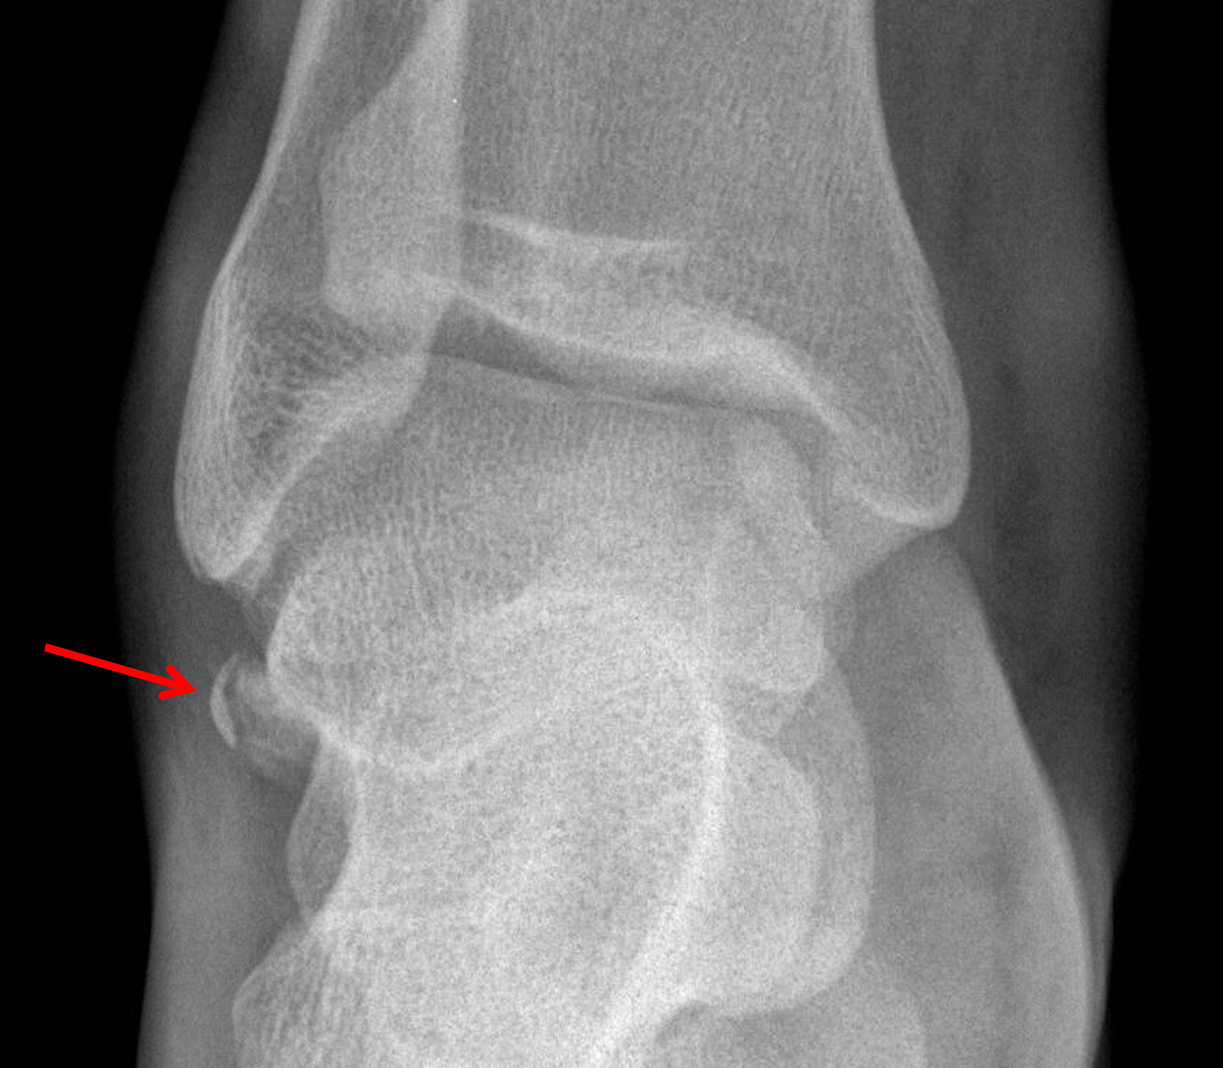

Lateral Talar Process Fractures FootEducation Talus Fracture X Ray View Recognition of the unique talar anatomy is important for correct diagnosis. Talar neck fractures are high energy injuries to the hindfoot that are associated with a high incidence of talus avascular necrosis. Talar fractures are an uncommon injury, accounting for <5% of all foot fractures. A skeleton model with the main bones of the foot labeled. Talus fractures (other than. Talus Fracture X Ray View.

Fracture of lateral process of the talus presenting as ankle pain Talus Fracture X Ray View Talar neck fractures are high energy injuries to the hindfoot that are associated with a high incidence of talus avascular necrosis. Talus fractures (other than neck) are rare fractures of the talus that comprise of talar body fractures, lateral process fractures,. A skeleton model with the main bones of the foot labeled. Recognition of the unique talar anatomy is important. Talus Fracture X Ray View.

Talus Lateral Process Fracture! Orthopaedics Talus Fracture X Ray View A skeleton model with the main bones of the foot labeled. Recognition of the unique talar anatomy is important for correct diagnosis. Talar fractures are an uncommon injury, accounting for <5% of all foot fractures. Talus fractures (other than neck) are rare fractures of the talus that comprise of talar body fractures, lateral process fractures,. Talar neck fractures are high. Talus Fracture X Ray View.